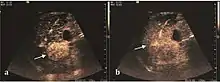

These lesions have various patterns (hypo or hyperechoic) with at least 1 cm diameter. They are hepatocytes with dysplastic changes, but without clear histological criteria for malignancy. They are divided into low-grade dysplastic nodules, where cellular atypia are mild and high-grade dysplastic nodules with moderate or severe cellular atypia, but without any established signs of malignancy. Occasionally, well-differentiated HCC foci can be identified in high-grade dysplastic nodules (appearance called "nodule in nodule") . Most authors accept the carcinogenesis process as a progressive transformation of DN from low-grade to high-grade and into HCC. The nodule's vasculature changes progressively, correlated with the degree of malignancy, and it is characterized by decrease until absence of portal venous input and by increase of arterial intratumoral input. Neoformation vessels occur with increasing degree of dysplasia. Arterial neovascularization is enhanced in a chaotic and explosive way, while normal, arterial and portal vasculature continues to decline. High-grade dysplastic nodules are hypovascularized both arterial and portal phases, while early HCC nodules may have similar arterial pattern with the surrounding parenchyma or exacerbated, and portal hypovascularization. In moderate or poorly differentiated HCC (classic HCC) tumor nutrition is performed only by neoformation vessels (abundant), the normal arterial and portal vasculature completely disappearing. This behavior of intratumoral vascularization is typical for HCC and is the key to imaging diagnosis.

B-mode ultrasonography is unable to distinguish between regenerative nodules and borderline lesions such as dysplastic nodules and even early HCC. Doppler examination also has a low sensitivity in differentiating dysplastic nodules from early HCC. Doppler signal may be absent in both regenerative and dysplastic nodules. Some authors indicate the presence of venous type Doppler flow which reflects the portal venous nutrition of the nodule as a characteristic feature of dysplastic nodules and early HCC (Minami & Kudo, 2010). Other authors noticed the presence of an arterial flow with small frequency variations and a normal resistivity index. On CEUS examination both RN and DN may have quite a variable enhancement pattern. Generally, both nodules enhances identically with the surrounding liver parenchyma after UCAs injection. Dysplastic nodules are hypovascular in the arterial phase. In case of highgrade dysplastic nodule sometimes a hypervascularization can be detected, but without associating "wash out" during portal and late CEUS phases. In these cases, biopsy may clarify the diagnosis.